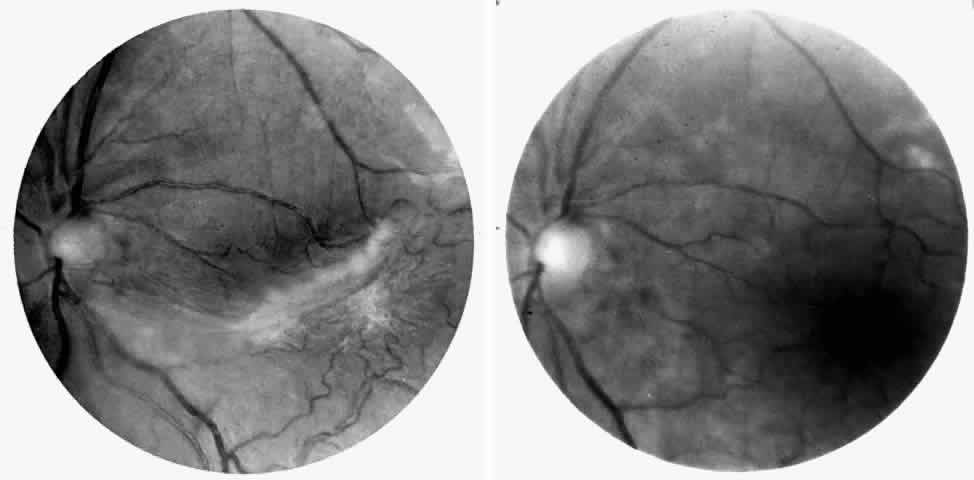

Angioid Streaks

Angioid streaks occur in association with sickle cell disease, with an overall incidence of less than 6%.72–75 The changes are more common in patients with homozygous sickle cell anemia and are age-dependent, occurring in 2% of sickle cell anemia patients less than 40 years of age versus 22% in those who are more than 40 years of age (Fig. 5).76

Fig. 5. A 45-year-old man with homozygous sickle cell anemia and angioid streaks (arrows).

Unlike the angioid streaks seen in patients with pseudoxanthoma elasticum, choroidal neovascularization and disciform disease are uncommon in association with sickle cell disease. Elastic tissue degeneration, as is seen in pseudoxanthoma elasticum, has not been demonstrated in the skin biopsy specimens of sickle hemoglobinopathy patients with angioid streaks.73,75 Initially, the etiology of angioid streaks in sickle cell disease was hypothesized to be secondary to iron deposition due to chronic hemolysis, causing brittleness of Bruch's membrane. Histopathologic examination of angioid streaks in a patient with homozygous sickle cell anemia, however, revealed heavy calcification of Bruch's membrane without evidence of iron or hemosiderin.77